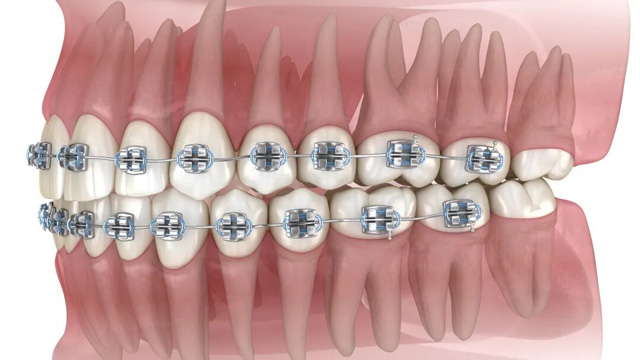

新桥口腔正畸全周期陪护,全程守护更安心

正畸是一场“持久战”,而智齿就是潜伏在暗处的变量因子,从正畸前评估到正畸后摘保持器,每个环节都很重要。作为深耕口腔正畸多年的老牌机构,新桥口腔推出系统化的“正畸全周期陪护服务”,从正畸方案定制到术后长期维养,全程守护,帮你规避风险、减轻顾虑,让正畸的每一步都更有保障。